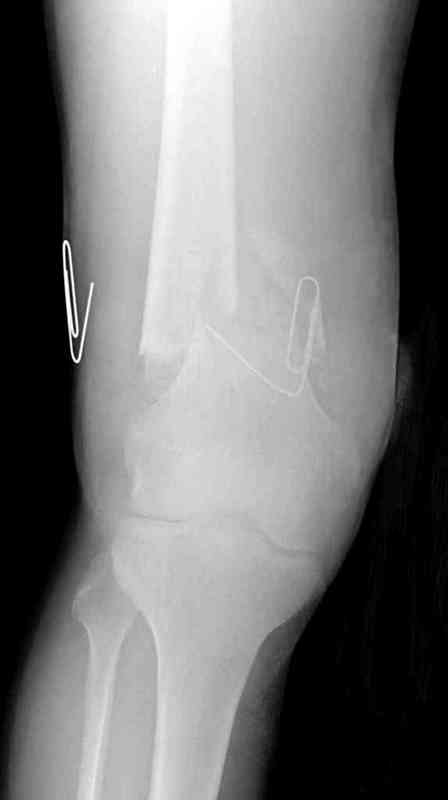

Пострадавшему 23, пистолетная огнестрельная не кроветочащая рана, меньше одного см диаметром, входное отверстие расположено латерально, и выход передне-медиально, и еще имеется второе пулевое ранение правой navicular bone с этой стороны.

Несмотря на сниженный до 0.9 BI-ankle-brachial-index (обязательное, недорогое исследование при подозрении на повреждение сосудов, рассчитанный по разнице давления в нижней и верхней конечности), последующее КТ ангиограмма не подтвердила повреждения артериальных сосудов.

Доступ был латеральный, при вскрытии с задней

поверхности бедра обнаружили кровотечение. Поднятием давления на заранее установленном турникете на конечности проконтролировали кровотечение.

В данном случае мы не ставили осуществление гемостаза приоритетным, после 30 минут больной оставлен вызванному сосудистому хирургу со стабильной фиксацией бедра. Несмотря на выбранный передне-медиальный доступ, хирург произвел восстановление сосудистого повреждения.

При близости сосудов к многооскольчатому повреждению костей, сперва необходимо удостовериться в наличии повреждения сосудов без применения турникета.

Сосудистые повреждения часто приводят к увеличению

давления в компартментах, мониторинг на голени показал увеличение, и поэтому сделана профилактическая латеральная фасциотомия.